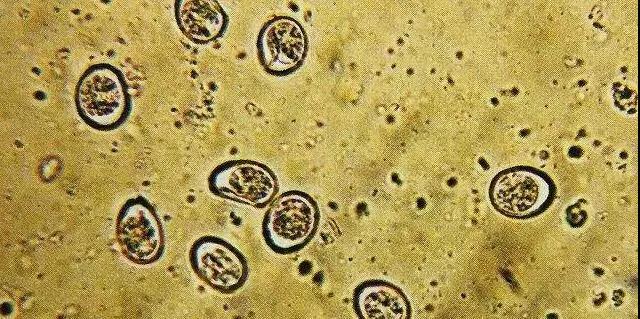

生理结构。球虫卵囊对普通的消毒药有极强的抵抗力,在土壤中可以存活 4~9个月。在有树荫的运动场可存活 15 ~18 个月。